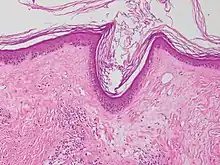

Micrograph of a vacuolar interface dermatitis with dermal mucin, as may be seen in lupus. H&E stain.